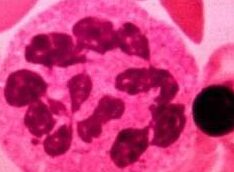

La anemia megaloblástica es un tipo de anemia caracterizada por la disminución de glóbulos rojos en la sangre. Esto puede ocurrir debido a deficiencias de vitamina B12 o ácido fólico, lo que afecta la producción adecuada de glóbulos rojos en la médula ósea.

El diagnóstico de la anemia megaloblástica se realiza a través de la evaluación de los síntomas por parte del médico y de pruebas de laboratorio. Un hemograma completo permite evaluar el número y tamaño de los glóbulos rojos en la sangre, lo que puede indicar la presencia de anemia megaloblástica.